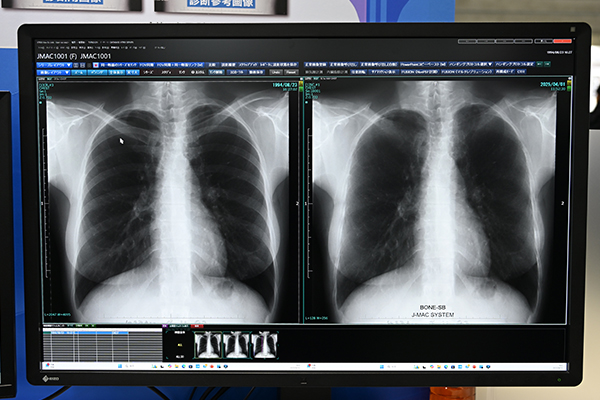

ジェイマックシステムでは,AIの開発を進めており,前回のITEMでも技術展示として開発中の機能を紹介してきた。今回はAIブランドとしてRely-AIを商標登録して,本格的に展開していくことをアナウンスした。Rely-AIの第一弾として発表したのが,肋骨減弱機能と心胸郭比計測機能である。両機能とも薬機法の承認を得ており,今後正式に上市する予定である。肋骨減弱機能は,胸部X線画像から肋骨を減弱処理して,視認性を向上。結節などを検出しやすくする。また,心胸郭比自動計測機能は,胸部X線画像から胸郭を自動で計測することで高精度かつ効率的な診断を支援する。病院をはじめ,健診センターなどの検診施設のように胸部X線撮影の検査数が多い施設,呼吸器科をターゲットに展開していくこととしている。

視認性を向上させる「Rely-AI」の「肋骨減弱機能」